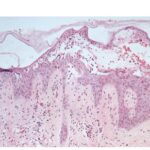

Histopathology. The earliest change consists of acantholysis in the upper epidermis, within or adjacent to the granular layer, leading to a subcorneal bulla in some instances . More commonly, enlargement of the cleft leads to detachment |

of the stratum corneum without bulla being seen. The number of acantholytic keratinocytes is usually small, often requiring a careful search to identify them. Secondary clefts may develop, leading to detachment of the epidermis in its mid level. These clefts may extend to above the basal layer, rarely giving rise to limited areas of suprabasal separation. In the setting of a subcomeal blister, dyskeratotic granular keratinocytes are diagnostic for this disorder. Eosinophilic spongiosis may be prominent with intraepidermal eosinophilic pustules. Thus, the histologic features of pemphigus foliaceus may have three pattems: {a} eosinophilic spongiosis; {b} a subcorneal blister, often with few acantholytic keratinocytes; and {c} a subcorneal blister with dyskeratotic granular keratinocytes , diagnostic of this disorder. The character of the inflammatory infiltrate is variable and depends on the age of the lesion, whether a blister is present, whether the superficial portion of the epidermis has been detached, and whether there is impetiginization or necrosis of the blister roof. |